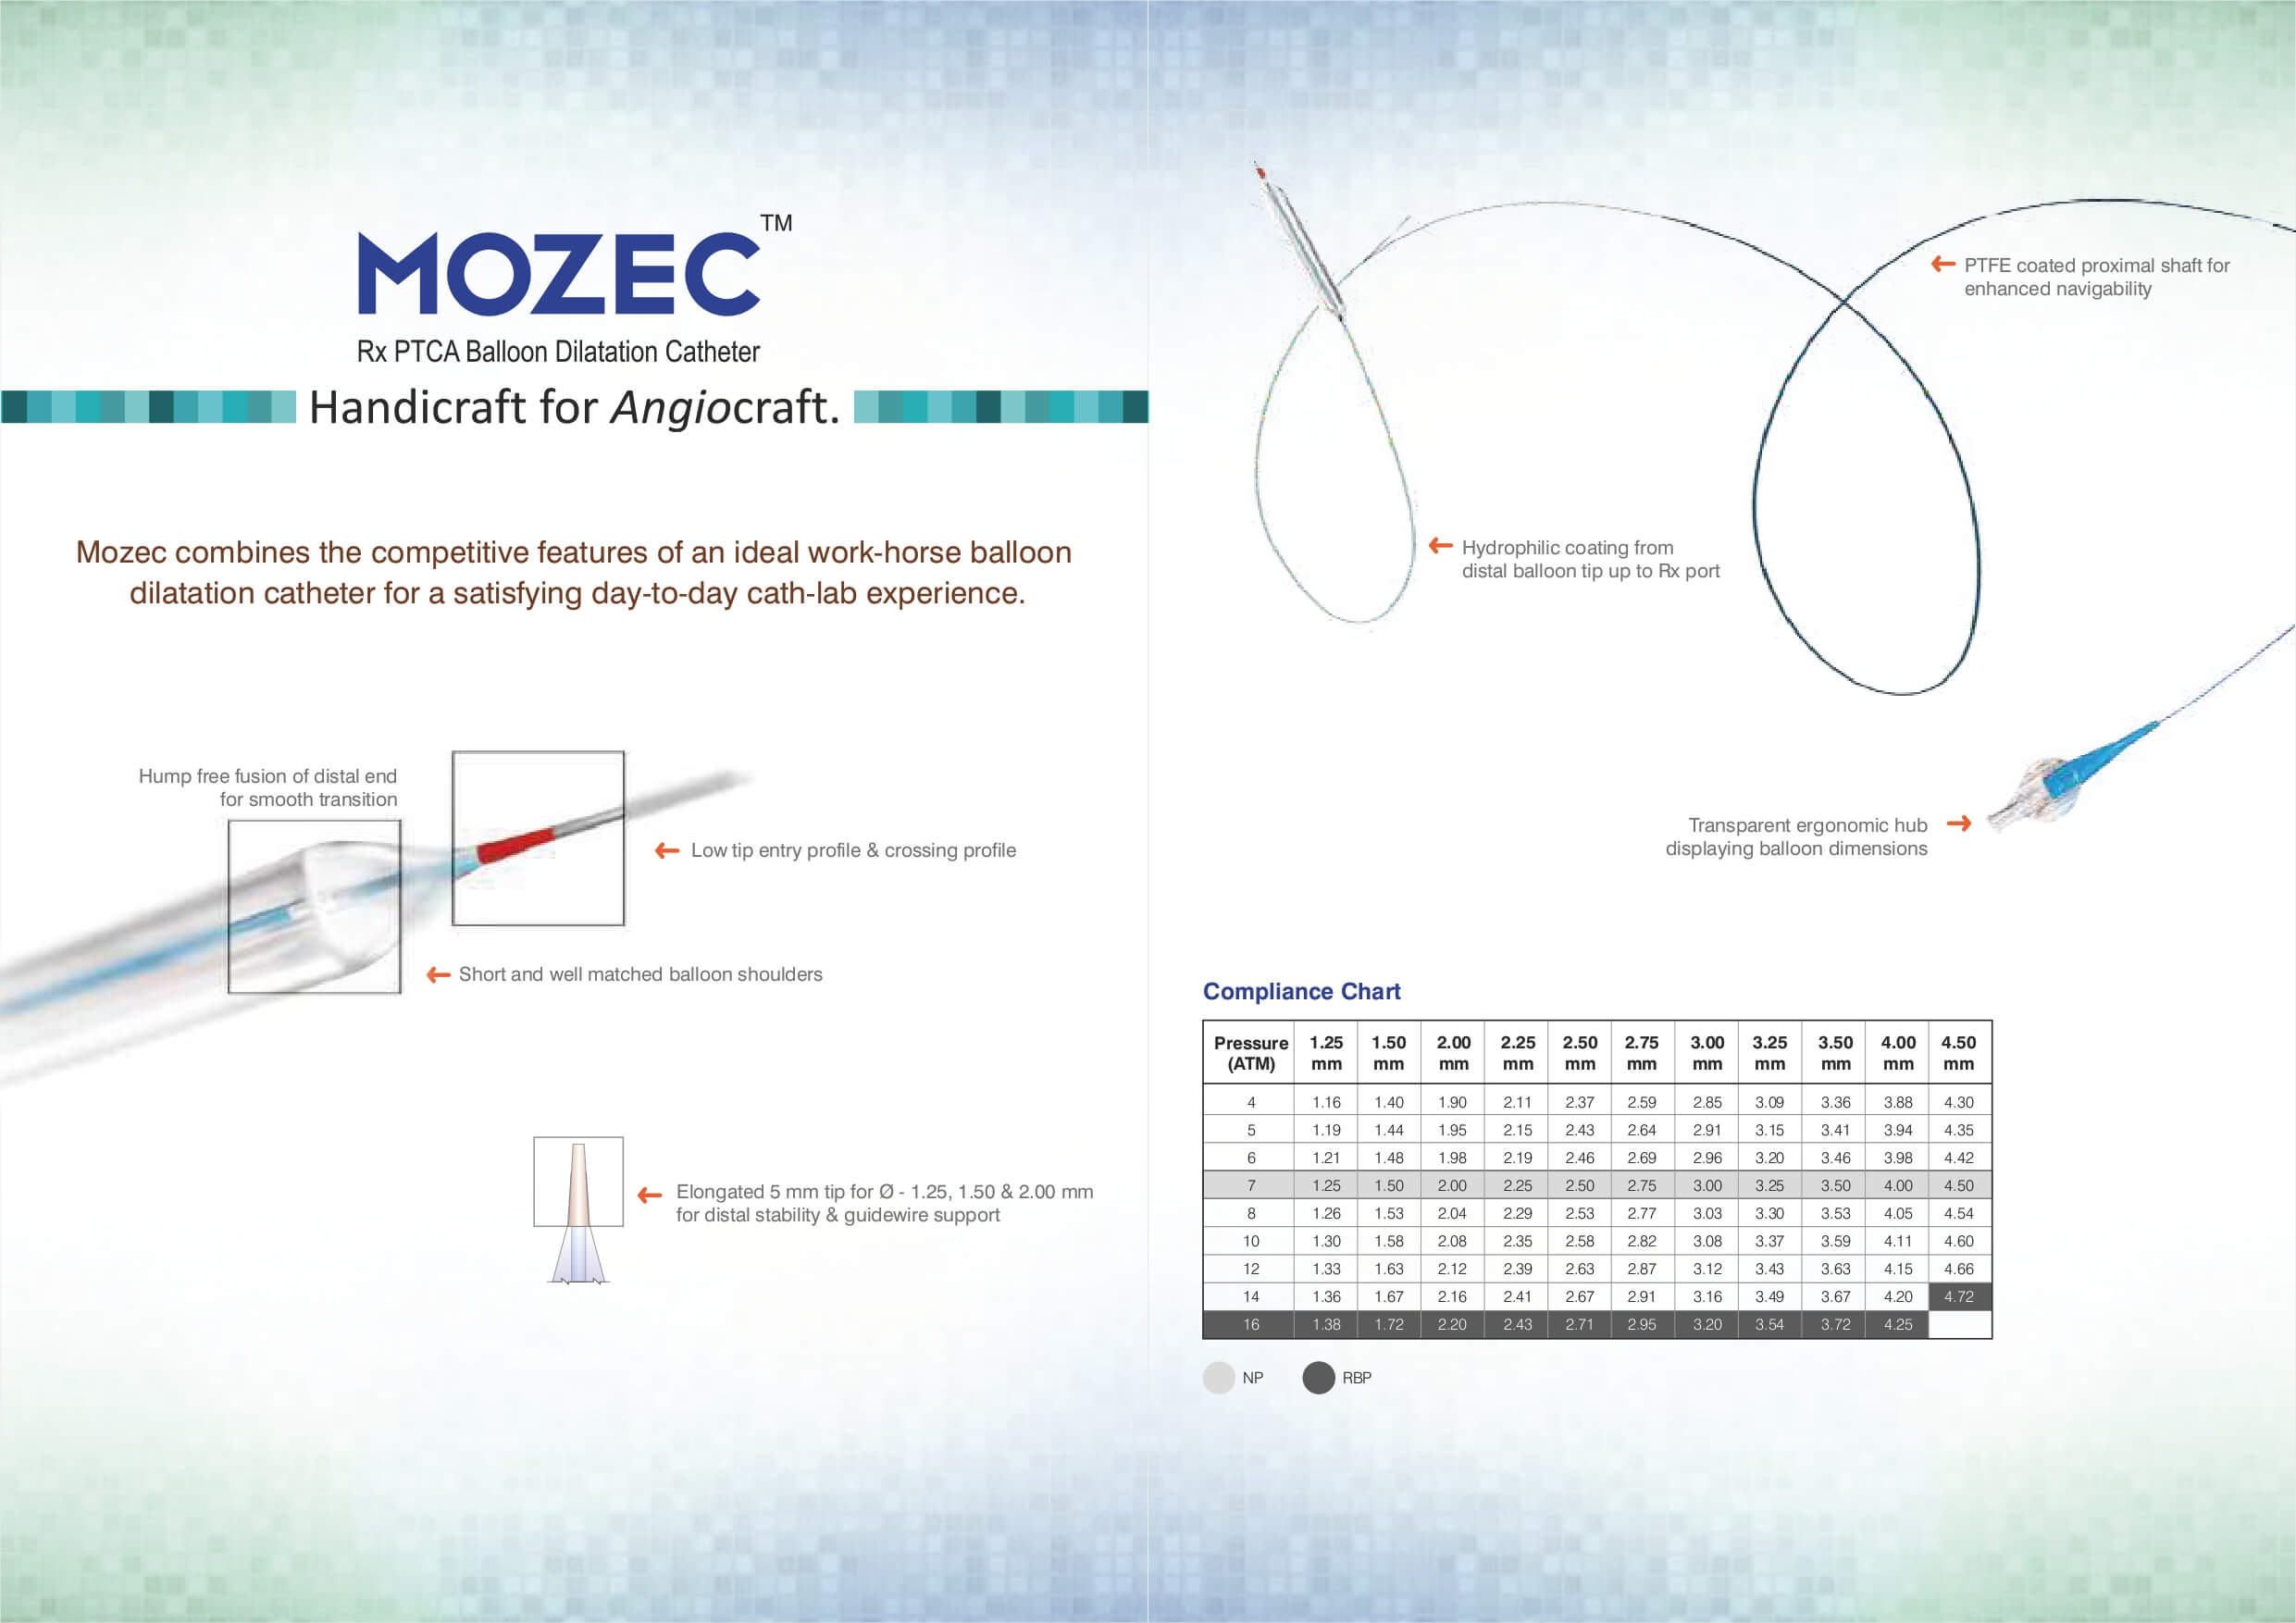

بالون دارویی کرونری MOZEC SEB برای انجام آنژیوگرافی، کاربرد دارد. این بالون از یک سیستم داروسازی جدید با فناوری نانو برای رها سازی کنترل شده دارو استفاده میکند و ویژگیهای خاص آن از نظر ابعاد، جنس و فشار قابل تحمل، این بالون را به گزینهای مناسب جهت انجام مداخلات عروقی تبدیل کرده است.